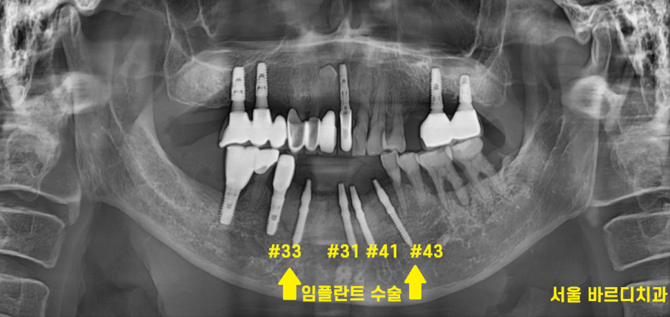

230627

발치 후 바로 강동구 치과에서

앞니 임플란트 수술을 진행하였습니다.

어금니는 이를 뽑고 기다리기도 하지만

앞니는 뼈가 얇아

주로 발치와 동시에 수술을 진행합니다.

6개의 앞니가 없었지만

4개의 임플란트 식립하고

머리는 6개로 만들어드리는 것으로

계획을 잡아 진행하였습니다.